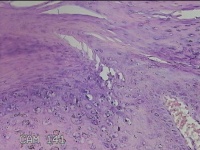

左手指结节

性别

男

年龄

42岁

临床诊断

皮下结节

一般病史

发现左手指结节2个月余。

标本名称

大体所见

灰白粉红色组织1x0.8x0.3cm一块,表面带梭形皮肤1x0.7cm,皮下见结节1x0.8cm,切开皮肤呈实性,切面灰白粉红色,质软。

图片无诊断价值。